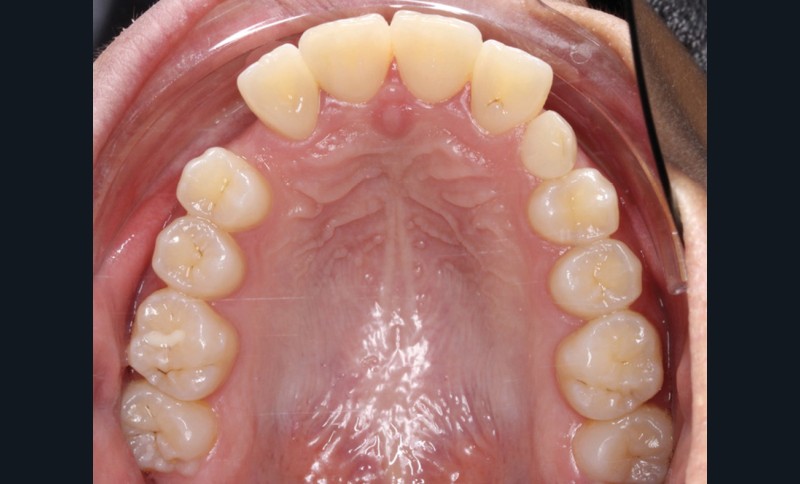

Les examens cliniques et radiologiques ont mis en évidence l’inclusion de 13 et 23, une légère classe II bilatérale par perte d’ancrage, un biotype parodontal de type IV de Maynard et Wilson avec une insertion du frein mandibulaire antérieur papillaire, une biproalvéolie et une typologie hypodivergente. La réalisation d’un examen tridimensionnel a permis de confirmer la localisation palatine de 23 et vestibulaire de 13 ainsi que de visualiser l’étendue des résorptions radiculaires touchant 12, 21 et 22 (fig. 1a-i).

Le plan de traitement choisi comprend les extractions de 63, 12, 22, 34 et 44. Ce choix s’est porté d’une part sur le fait de la présence de résorptions très avancées de 12 et 22 et d’autre part sur la correction de la biproalvéolie facilitée par l’extraction de 34 et 44 qui ont par ailleurs un diamètre légèrement inférieur à 35 et 45.

Un appareil multi-attaches .022 x .028 (prescription de Roth) est posé sur toute l’arcade mandibulaire et sur les secteurs postérieurs maxillaires (17 à 14 et 27 à 24) afin d’éviter au maximum la sollicitation de 11 et 21 et donc de limiter les résorptions radiculaires.